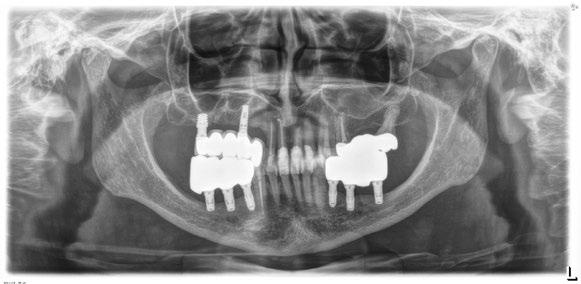

Figura 17. Radiografía final del caso con las prótesis definitivas, tras dos años de seguimiento, sin pérdidas óseas evidentes en ninguno de los implantes estudiados.